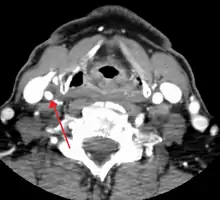

CT image of a 70 percent stenosis of the right internal carotid artery

Carotid artery stenosis is usually diagnosed by color flow duplex ultrasound scan of the carotid arteries in the neck. This involves no radiation, no needles and no contrast agents that may cause allergic reactions. This test has good sensitivity and specificity.[16]

One of several different imaging modalities, such as a computed tomography angiogram (CTA)[18][19][20] or magnetic resonance angiogram (MRA) may be useful. Each imaging modality has its advantages and disadvantages - Magnetic resonance angiography and CT angiography with contrast is contraindicated in patients with chronic kidney disease, catheter angiography has a 0.5% to 1.0% risk of stroke, MI, arterial injury or retroperitoneal bleeding. The investigation chosen will depend on the clinical question and the imaging expertise, experience and equipment available.[21]